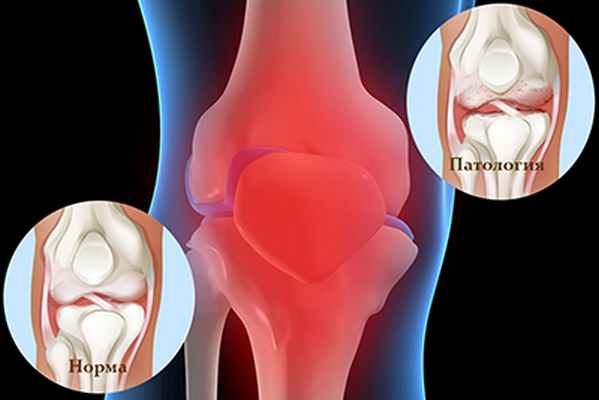

Строение коленного сустава, вид спереди

Наиболее распространенной формой суставной патологии является остеоартоз. Это заболевание, при котором в патологический процесс вовлекается весь сустав, включая подхрящевой участок кости, капсулу, связки, синовиальную оболочку, околосуставные мышцы.

Гонартроз

Это остеоартроз коленного сустава. Болезнь обычно развивается так незаметно, что пациент затрудняется указать давность заболевания. Отмечаются периодический хруст при сгибании, эпизодические тупые боли после выраженной и длительной нагрузки на сустав, которые быстро проходят после её прекращения. Постепенно их интенсивность усиливается, плохо переносится уже любая нагрузка, боли могут появляться ночью.

Клинические проявления гонартроза начинаются обычно в старшем возрасте, после 40-50 лет, у женщин чаще во время менопаузы. Он может быть: